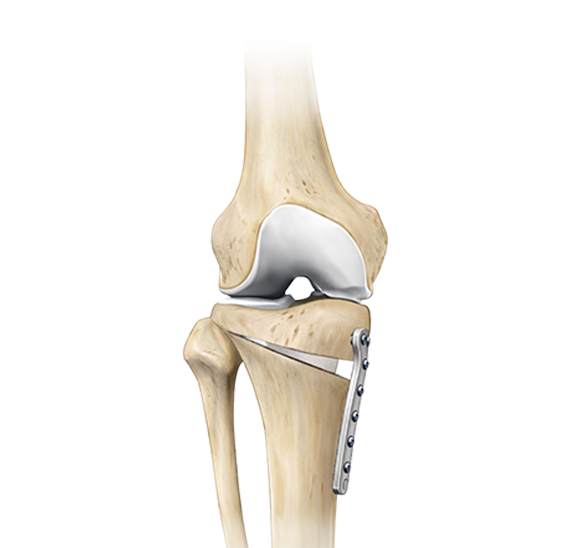

근위경골절골술은 오다리 변형으로 인해 무릎 안쪽 관절에 집중되는 체중 부하를 교정하기 위한 수술입니다.

무릎 아래 뼈인 경골의 정렬축을 조정하여, 이를 통해 무릎 안쪽 연골에 집중되던 부담을 줄이고 통증 완화를 기대할 수 있습니다.

여기에 연골의 근본적인 재생을 유도하는 줄기세포(카티스템) 연골재생술을 결합한다면 무릎 관절의 수명을 늘리는데 더욱 도움이 됩니다. 결과가 좋은